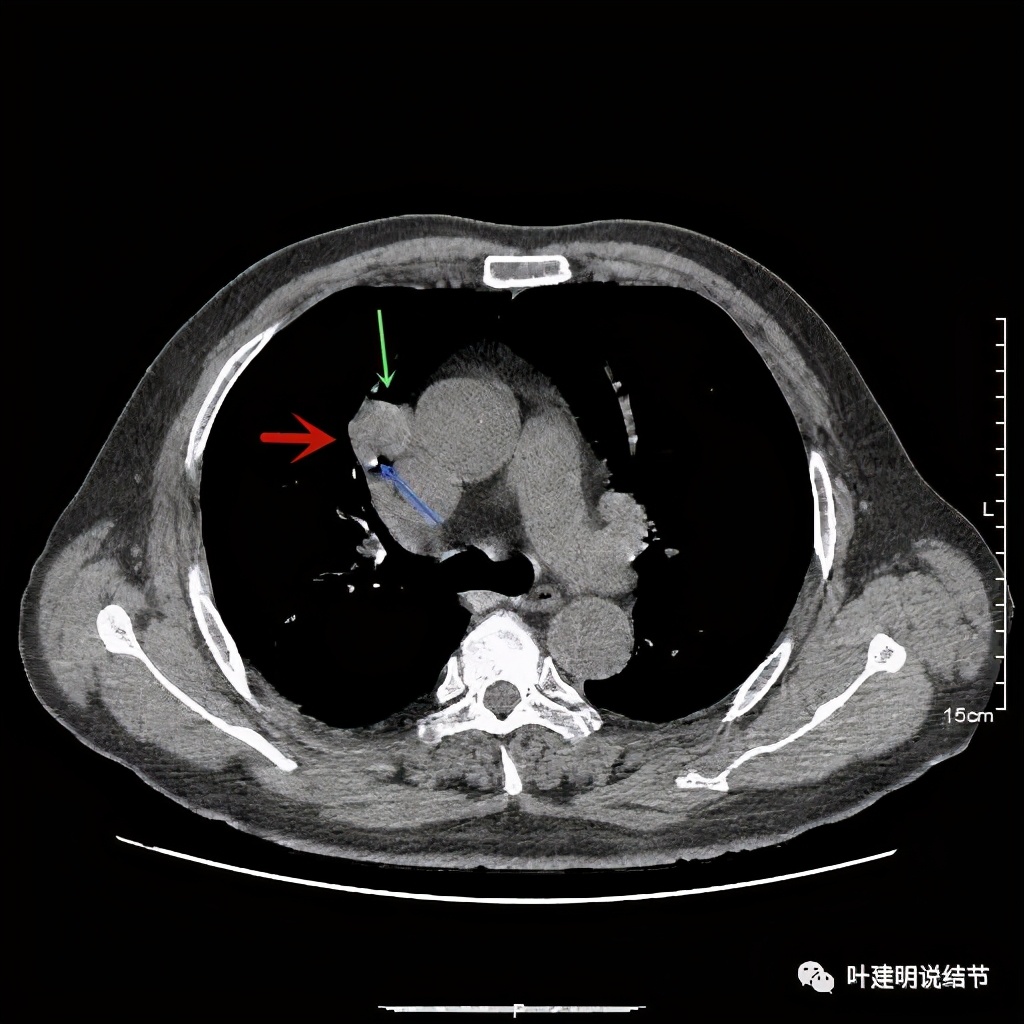

直径约2.4厘米,密度欠均,血管贴边,增强轻度强化。单从描述看,恶性可能性较大。我们再来看看图像:

可见右上叶占位,我们现在知道了结果以后回头看,发现病灶的边缘在各个层面都是过于光滑(绿色箭头所示)。血管紧贴病灶边走行(桔色箭头所指),是不是有侵犯看不清楚,若是靶扫描加重建可能会更清楚点。支气管感觉也是贴着病灶走,但有的层面是不是截断,也不看的不太清楚。有的层面见局部有点状高密度(蓝色箭头所指),是不是错构瘤的局部钙化呢?若是纵隔窗又是如何?

上图示病灶